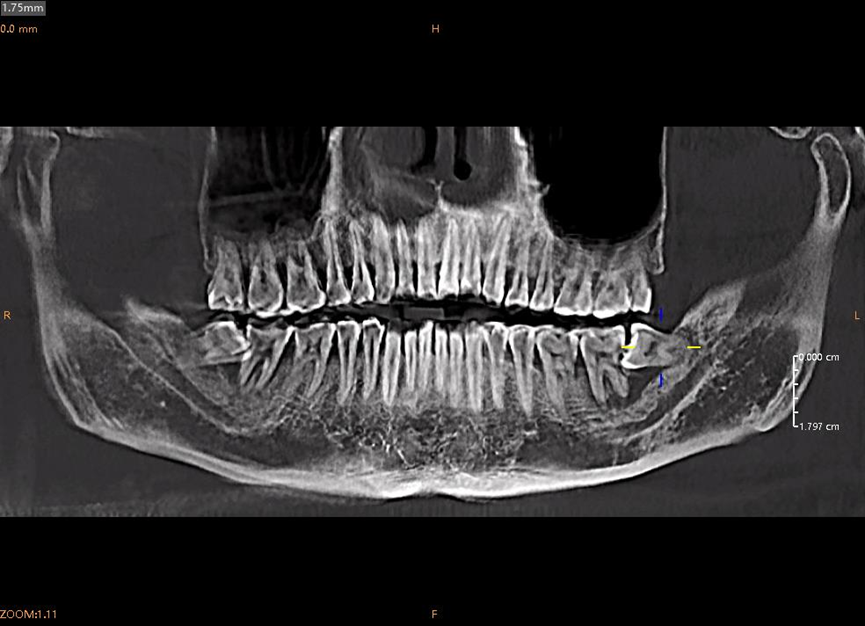

CT影像显示更是触目惊心:左下第7磨牙牙根几乎被完全吸收,智齿横着挤压邻牙,右下同样埋伏着两颗"定时炸弹"。

"牙龈萎缩到根尖都露出来了,牙槽骨吸收过半,这颗牙就像站在悬崖边上,平时刷牙出血没当回事吧?”胡医生叹气,“牙周炎是慢性病,等感觉到疼,骨头早就‘啃’没了。”

刘先生口腔全景图-实拍